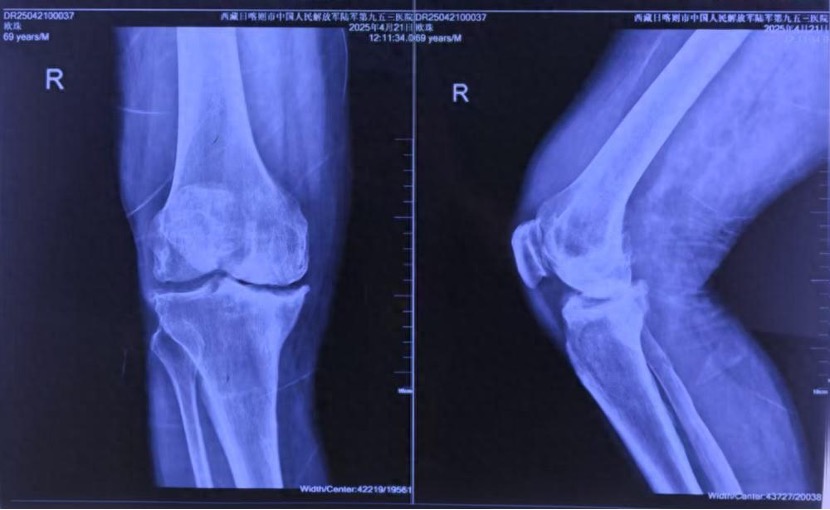

69岁的藏族老人欧珠(化名)常年受双膝疼痛折磨,右膝严重内翻畸形伴骨缺损,步行百米即需歇息。张瑗介绍,如果对老人实施传统手术,则面临三大难题,一是患者骨骼“塌方式”缺损,假体匹配难度倍增;二是医生需克服高原反应,设备需在低压低氧环境中稳定运行;此外,生物膝标准严苛,截骨误差需小于1毫米,压力失衡将导致假体寿命骤降50%。

▲患者术前CT。新桥医院供图